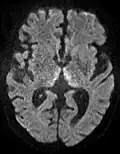

The most common application of conventional DWI (without DTI) is in acute brain ischemia. DWI directly visualizes the ischemic necrosis in cerebral infarction in the form of a cytotoxic edema,[38] appearing as a high DWI signal within minutes of arterial occlusion.[39] With perfusion MRI detecting both the infarcted core and the salvageable penumbra, the latter can be quantified by DWI and perfusion MRI.[40]

DWI showing restricted diffusion in the medial dorsal thalami consistent with Wernicke encephalopathy -

Cerebral infarction leads to diffusion restriction, and the difference between images with various DWI weighting will therefore be minor, leading to an ADC image with low signal in the infarcted area.[24] A decreased ADC may be detected minutes after a cerebral infarction.[26] The high signal of infarcted tissue on conventional DWI is a result of its partial T2 weighting.[27]